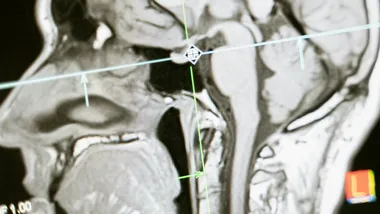

Дослідження, проведене науковцями Київського національного університету імені Тараса Шевченка, вперше розкрило глибокі нейрофізіологічні зміни в роботі мозку під час повномасштабної війни. Унікальне наукове дослідження демонструє, як хронічний стрес впливає на когнітивні здатності людини та її здатність виконувати розумові завдання.

Науковці на чолі з докторкою біологічних наук Марією Черних провели масштабне дослідження, залучивши 57 добровольців різного віку. Учасників було розподілено на дві групи: контрольну групу, обстежену до повномасштабного вторгнення, та групу воєнного періоду. Дослідження фокусувалося на аналізі електроенцефалографічної (ЕЕГ) активності мозку під час виконання ментальних арифметичних завдань.

Методологія дослідження передбачала реєстрацію електричної активності мозку за допомогою сучасного обладнання Neurocom. Учасникам пропонували виконати послідовні математичні обчислення подумки, while їхня мозкова активність реєструвалася в різних частотних діапазонах, зокрема в альфа-ритмі.